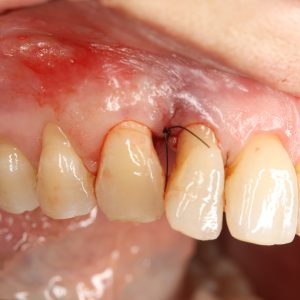

Image C1:1 Pre-Operative (Tooth 12)

Approximately 9 mm periodontal pocket distally, and approximately 4 mm buccal recession.